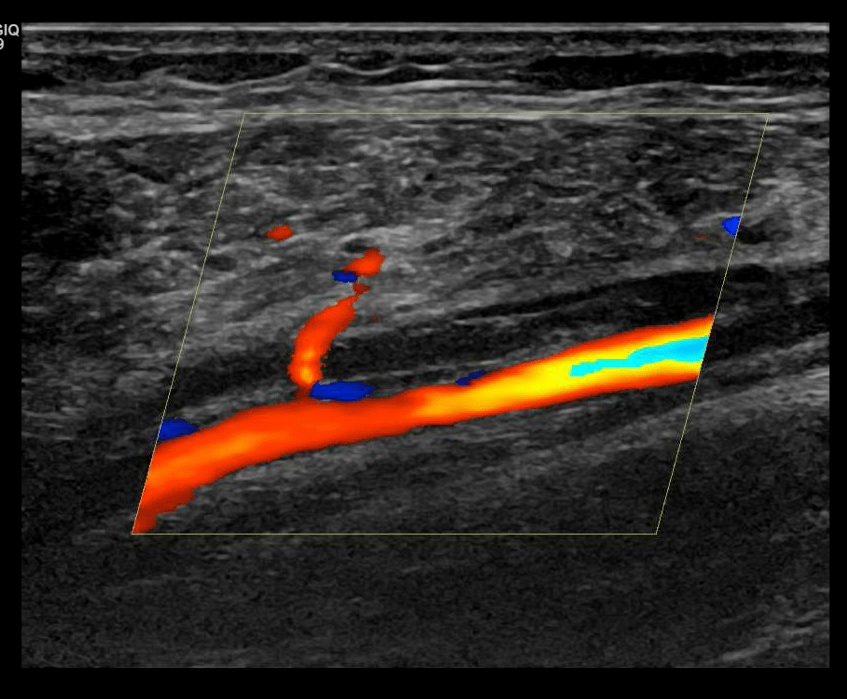

DVT of the subvlavian

Scan the subclavian vein in grey scale, color doppler and spectral doppler